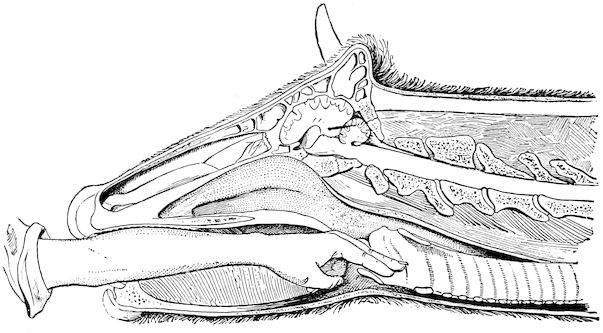

Fig. 4.—Deformity of the face in the horse shown in Fig. 2.

The flat bones are particularly liable to this change, which is common to domesticated animals. The bones of the head are the first to suffer; later those of the pelvis. The lower jaw becomes swollen, particularly about the centre of the branches which may attain three, four, or five times, their normal thickness.

The depression in the submaxillary space disappears. The upper jaw undergoes similar changes, becoming deformed and thickened until the cavities of the sinuses and the hollow appearance of the palate are lost, while the face is so changed that it cannot be recognised as that of a horse, goat, etc.

The molar teeth are almost buried, their tables alone being visible at the bottom of a depression, the edges of which rise above the neighbouring parts (pig).

Mastication is clearly impossible, the jaws appear paralysed, the muscles powerless, and only swallowing is possible, a fact which explains why life is only prolonged to this stage in animals which can be fed with a spoon or bottle (pigs and goats). The bones of the cranium, although greatly changed in texture, are always less deformed than those of the face.

The changes are such that it is often easy with a mere post-mortem knife to cut the head completely in two. Osseous tissue, properly so-called, has disappeared.

All the constituent tissues, with the exception of the skin and muscles, i.e., the bone, periosteum and aponeuroses, have the appearance and consistence on section of the fibro-lardaceous tissue seen in chronic inflammation.